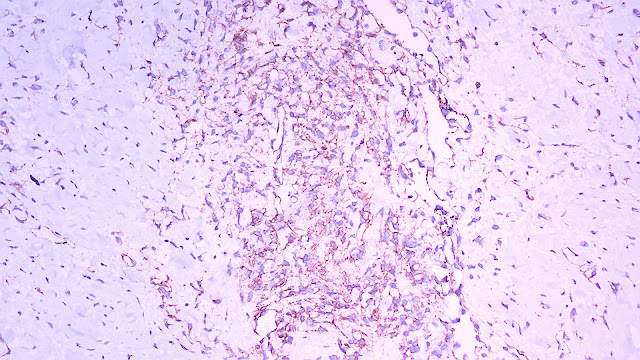

INMUNOHISTOQUÍMICA:

HHV-8

CD34

CD31

Biopsia

Canales vasculares anormales y anastomosados

Los bordes son infiltrantes y no están bien circunscritos

En los tumores poco diferenciados, puede haber áreas sólidas fusiformes o epitelioides sin formación evidente de vasos.

Un panel de marcadores de antígenos endoteliales y epiteliales puede ayudar a distinguir el AS del carcinoma poco diferenciado